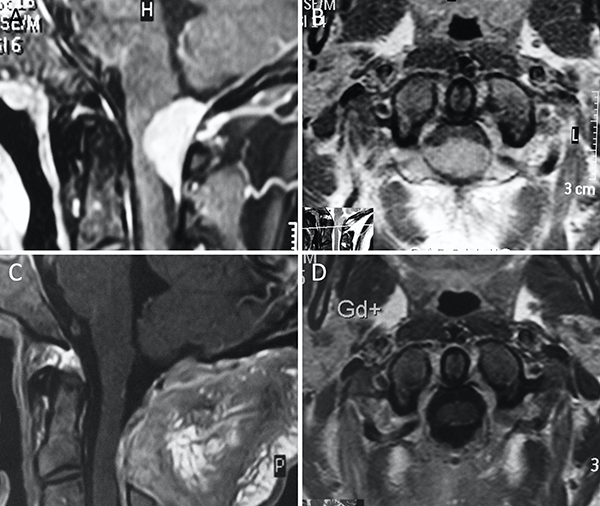

Figura 9. Meningioma del foramen magno anterior. A-B: RM preoperatoria; C-D: RM postoperatoria.

Figura 10. Meningioma del foramen magno lateral. A-B: RM preoperatoria; C-D: RM postoperatoria.

Figura 11. Meningioma del foramen magno posterior. A-B: RM preoperatoria; C-D: RM postoperatoria.